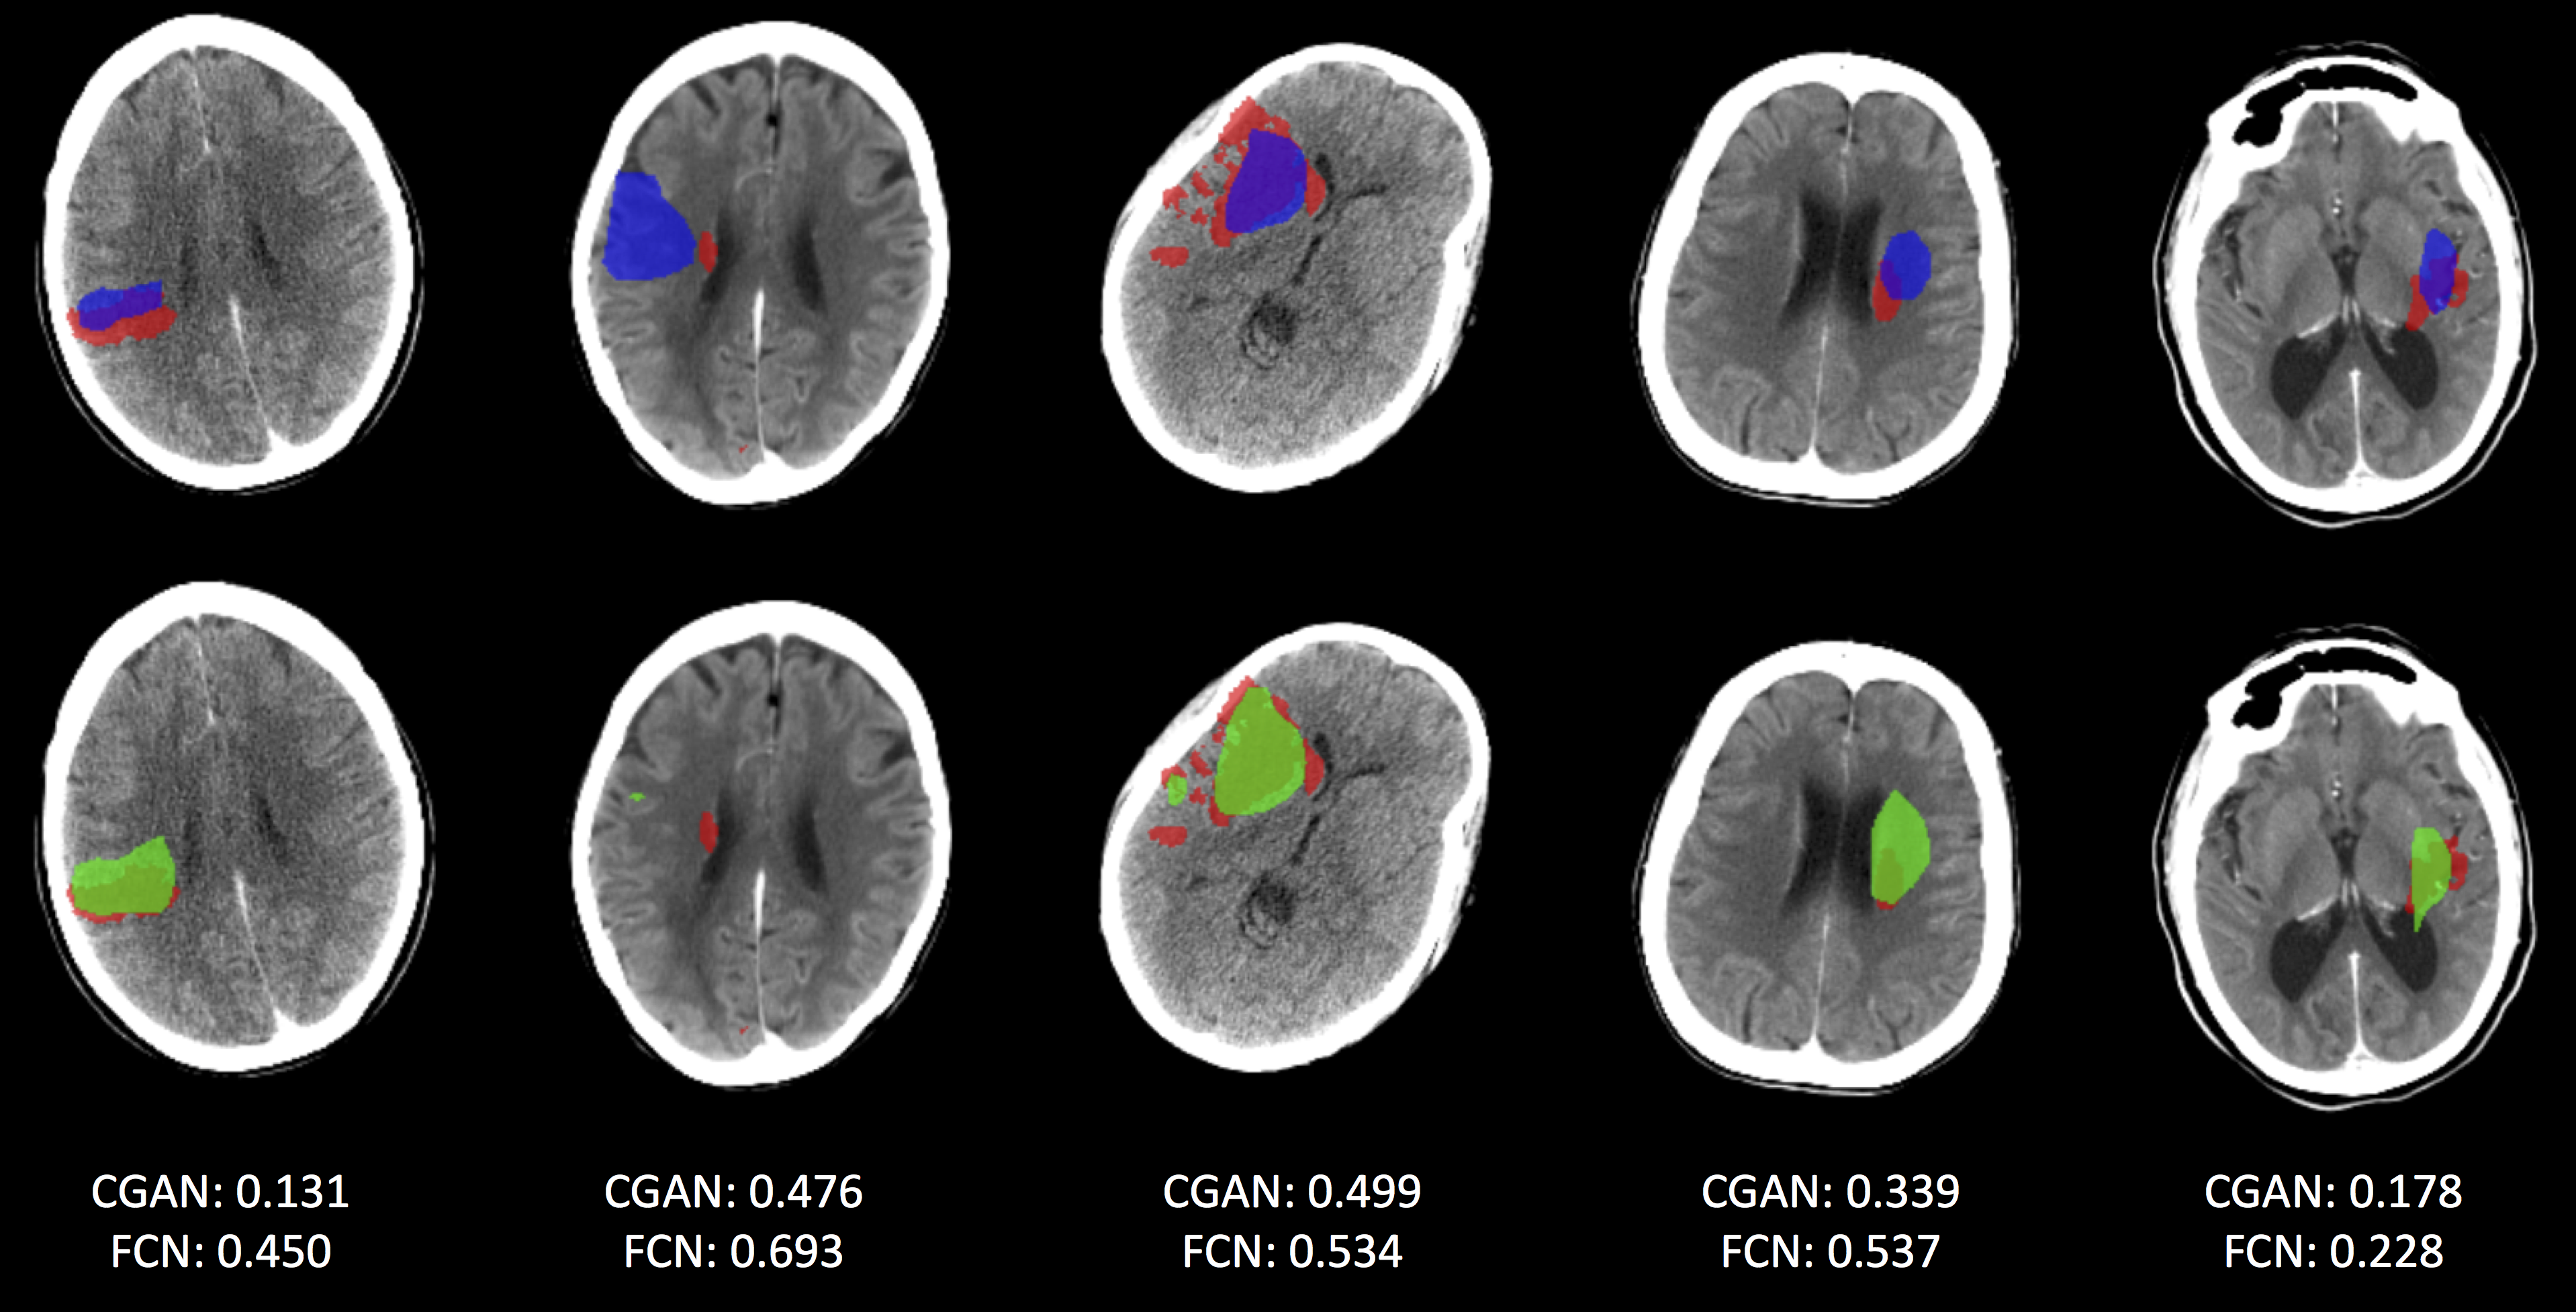

Figure 4: A comparison of segmentation results for scans where the FCN model performs better than the FCN-CGAN model. As in Fig. 3, the top row shows results from the FCN-CGAN and the bottom row shows those from the FCN model. Coloring information is the same as in Fig. 3. Overall dice score for each scan is also shown.

Of course, given the overall moderate performance improvement of the FCN-CGAN model, there do also exist scans where the FCN model performs better than the FCN-CGAN model. Fig. 4 shows these cases, where once again the top row represents FCN-CGAN lesion predictions in blue and the bottom row shows FCN lesion predictions in green. We see an interesting failure case in the 2nd scan from the right in Fig. 4, where both models have failed to predict the ground truth ischemic core region in red, however the FCN-CGAN model generates a much larger over-prediction than the FCN model for this case.